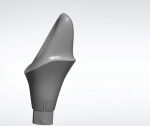

Custom Abutment Design

Proper emergence and margin depth have always been important. However, understanding the client's challenges with cementation and post-cementation protocols will help the laboratory design its next patient-specific abutment more appropriately (Figure 1). While tissue bio-type can be challenging with titanium abutments, the best thing to do is to place the margin heights close to equigingival with the sulcus-starting at the mesial and moving around the lingual to the distal. This will allow for a "vent" and easier cement clean-up, since any excess cement will vent out and be easily seen by the clinician.

Additionally, when designing abutments, pay close attention to how the crown emerges from the abutments, a detail that is equally important. Proper understanding of machining constraints on margin preparation design will help to make the transition from abutment to crown more uniform. A thick margin line offset is not conducive to an optimum transition interface, and instead there should be a seamless transition between the abutment and the cemented crown.